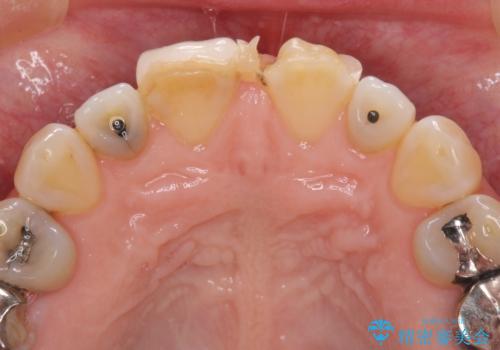

- 前歯のすきっぱを主訴にご来院された患者様です。他院でつめものやラミネートべニア(前歯の表面のみセラミックを貼り付ける)を行っていましたが、頻繁に外れることに悩まれており、クラウン(歯全体をセラミックがつつむ)をご希望されました。また、奥歯に大きな虫歯があり、歯が割れていたため、奥歯の治療も併せて行いました。

今回はまず欠けた場所を修復して見た目を回復させたのち、ラミネートべニアの仮歯をつくり、しばらく使用して考えて頂きました。メリットやデメリットを説明した結果、外れにくいセラミッククラウンをご選択頂きました。

咬み合わせや元のご自身の歯の色に特徴があったため、セラミッククラウンを修正したり、隣の歯を金属を外して白いつめものに変えたりして経過観察を長めに行いました。

右上の歯に関しても、大きな虫歯があったため、前歯の経過観察の間に治療を行いました。